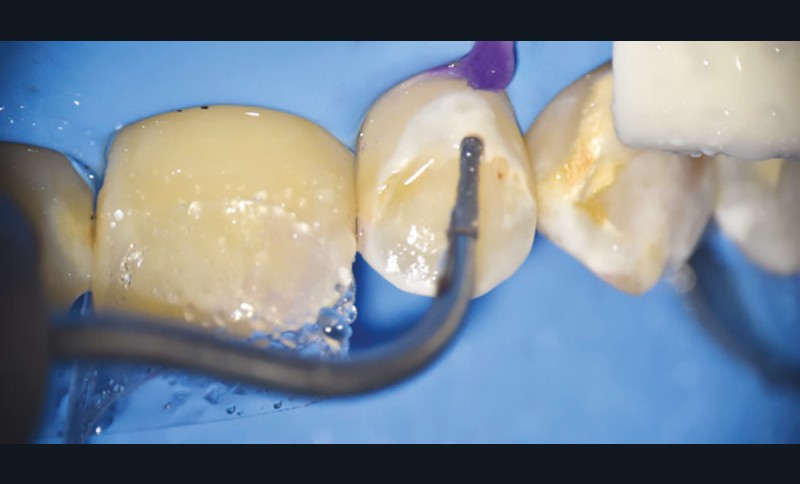

- soit de façon invasive a minima. Cette économie tissulaire peut se faire notamment avec l’utilisation de fraises adaptées et minimalement invasives (fig. 4).

• Traitement invasif a minima : il concerne les lésions carieuses cavitaires ou non avec atteinte dentinaire (à partir du 1/3 moyen dentinaire), soit ICDAS 3 à 6. Dans ce cas, la priorité est de préserver la dent d’une effraction pulpaire éventuelle (recommandations de l’ESE) [4]. C’est pourquoi, lors du traitement de lésions carieuses profondes (ICDAS 4 à 6), il faut dans tous les cas réaliser une éviction sélective, réaliser une préparation a minima (favoriser les préparations de type fente (« slot ») ou tunnel lorsque l’indication se pose) et utiliser un matériau de restauration de choix, soit composite, soit un ciment verre ionomère (CVI), soit des matériaux à base de silicate de calcium ou encore les nouveaux composites enrichis en minéraux (fig. 7 à 9). Ces préparations a minima peuvent être réalisées avec des fraises de petits diamètres (fig. 10 et 11).